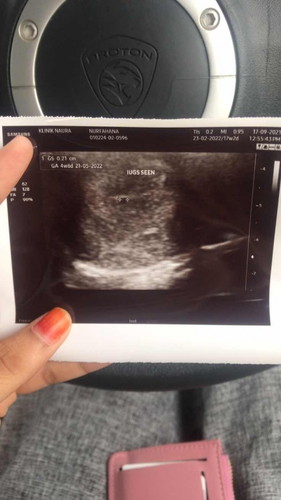

Scan 4w6d nampak kantung je

Hi mommy , normal ke kalau 4w6d scan nampak kantung lg ? Sebab masa saya scan tu kantung dah nampak tapi kecik lg la .. Lepastu doc ckp lepas 3mggu dtg blik untuk scan heartbeat .. so means time tu saya dh 8w bersamaan 2m lah kan .. skrg ni bru 5w2d .. mohon pencerahan risau π sbb firstbaby and dh lama tggu dy #firstbaby #bantusharing #1stimemom #seriusnanya